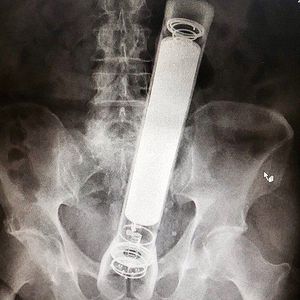

Foreign body in lower abdomen

Body

Abdomen

Foreign